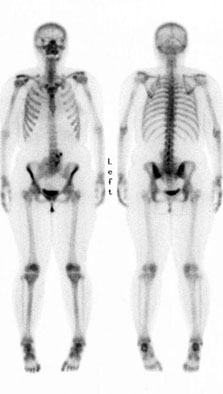

- 骨スキャン(左図)では腎臓から排泄されるので、正常な腎機能があれば腎臓と膀胱のactivityも当然見られる。この症例では正常の位置に腎臓の形態が見られないのが診断のポイントであった

- 骨スキャンでは腎臓も忘れないように気をつけましょう。